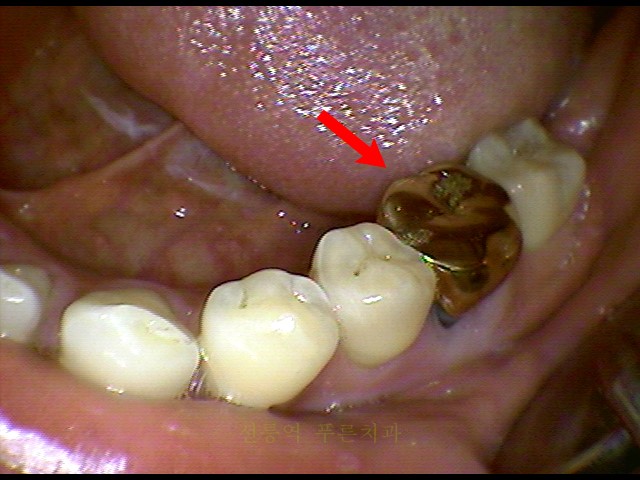

오늘의 주제는 잇몸 농포입니다. 치과 방문 중에 잇몸에 농양이 있는 환자를 많이 보았기 때문에 이 주제를 선택했습니다. 먼저 치은 농양이 어떻게 생겼는지 살펴보겠습니다.

여기도 멋져보입니다. 여기 당신이 지금 이해하는 것이 있습니까? 여기있어. 잇몸에 있는 이러한 농포는 생각보다 쉽게 발견할 수 있습니다. 기술적으로는 누공이라고 합니다. 치아 내부의 염증은 뼈를 뚫고 잇몸 밖으로 나올 수 있습니다. 그러나 이런 일이 발생하면 일반적으로 통증이 없습니다. 환자들은 종종 “어느 순간부터 나오기 시작하다가 피곤해지면 올라왔다가 없어진다”고 말합니다. 고름 주머니는 보통 통증이 없습니다. 다른 주요 증상은 없습니다. 그렇다면 잇몸에 고름 주머니가 생기는 원인을 알아보겠습니다. 잇몸 고름 주머니가 부착된 위치를 확인하여 확인할 수 있습니다. 뼈의 염증은 잇몸에 고름 주머니가 형성되기 전에 먼저 발생합니다. 그러면 뼈에 염증이 생기는 이유는 치아에 문제가 있는 것인데 치아에 세균이 있으면 세균이 뼈에 염증을 일으키게 됩니다. 궁극적으로 잇몸의 고름 주머니는 치아 내부의 박테리아에 의해 발생합니다. 이로써 치주낭으로 치아를 치료한다고 생각할 수 있습니다. 치아 내부의 세균을 제거하는 것입니다. 바로 신경외과를 통해서입니다. 이미 근관치료를 받은 치아는 근관치료가 필요합니다. 결국 관건은 근관이나 신경재배치를 얼마나 잘 했는지, 치아 내부를 얼마나 잘 닦았느냐다. 각각의 경우를 살펴볼까요? 보자. 치근 치료를 받은 치아의 고름 주머니. 치아 뿌리에 염증이 생겼습니다. 치료는 신경치료입니다. 이렇게 신경재배치로 치료를 마치면 이렇게 고름주머니가 사라집니다. 모든 뿌리 염증이 사라졌습니다. 전후가 달라요 이런 경우처럼 신경치료 후 염증이 생긴 경우가 생각보다 많은데 이번에는 또 다른 경우입니다. 절치신경치료와 크라운치료를 시행한 사례입니다. 잇몸에는 두 개의 고름 주머니가 있습니다. 치료방법은 당연히 재신경치료로 치관을 제거하고 재신경치료를 시행합니다. 중국에서는 치료지만 가장 기본이 아닌… 치료입니다. 그러나 후퇴는 어렵다. 재신경치료가 잘되면 뿌리의 염증은 사라진다. 물론 농양도 사라집니다. 세 번째 경우에는 왼쪽 위 어금니 뿌리에 염증이 생기고 고름 주머니가 생겼습니다. 치료방법은 당연히 재신경치료인데 심장으로 재신경치료를 하면 염증이 근본적으로 사라집니다. 뿌리의 고름주머니도 없어졌고, 신경치료를 받은 오른쪽 위 어금니에도 염증이 생겼다. 그리고 농포. 이 각도에서 보기가 힘드네요 암튼 신경치료를 위해 병원을 여러번 다니며 치료를 이어갈 예정입니다. 크라운을 제거한 후 포스트의 헤드를 보강하기 위한 포스트가 있습니다. 그래도 다 떼고 치료하세요. 게시물을 삭제하지 않으면 복구되지 않습니다. 컬럼을 제거하고 더 많은 내부 포장재를 제거해야 합니다. 그런 다음 농포가 사라졌습니다. 지금까지의 경우를 보면 모두 근관치료를 받은 염증치아입니다. 염증은 치료되지 않은 치아의 뿌리에서도 발생할 수 있습니다. 뿌리의 염증. 고름 주머니가 있습니다. 이런 치아 염증의 원인은 치아 내부가 괴사되었기 때문입니다. 치아 내부 충치의 원인은 다양합니다. 충치 때문입니다. 외상성 물기 때문입니다. 바깥 치아 때문입니다. 따라서 치아가 내부적으로 죽으면 치아 뿌리에 염증이 생겨 고름 주머니가 생길 수 있습니다. 치료법은 당연히 신경외과다. 이 환자분의 경우는 크라운이 아니라 레진으로 했습니다. 다음과 같은 경우 왼쪽 아래 치아 뿌리에 염증이 있습니다. 염증은 기존 충전물의 문제 또는 치아에 너무 많은 힘을 가하는 교합 관계로 인해 발생할 수 있습니다. 큰 농양이 있습니다. 방사선 사진에서 치아의 뿌리는 해부학적으로 변위된 치아입니다. 신경치료는 다른 치아에 비해 성공률이 낮지만 치료는 계속 진행하고 있습니다. 신경 치료 후 치아 뿌리의 염증도 가라 앉았습니다. 고름 주머니도 사라집니다. 이러한 방식으로 치료하지 않은 치아도 뿌리에 염증이 생겨 시간이 지남에 따라 고름 주머니가 형성될 수 있습니다. 일단 고름 주머니가 생기면 저절로 사라지지 않습니다. 치근에 염증이 생기면 시간이 지남에 따라 크기가 커지는 것처럼 보일 수 있습니다. 그러나 일단 고름 주머니가 형성되면 무한정 자라지 않습니다. 농포가 배출하는 방법이라고 생각하십니까? 하지만 앞서 말씀드린 것처럼 신경치료, 신경재신경치료, 발치 등을 하지 않는 이상 저절로 없어지지는 않습니다. 입안에 고름이 차있다면 치아 내부에 이상이 있을 가능성이 높기 때문에 근관치료나 재신경치료로 치료가 가능하니 가까운 치과에서 꼭 확인을 받아보시길 바랍니다 . 다라플랜트치과입니다. 끝까지 읽어주셔서 감사합니다. 질문이 있으시면 댓글을 남겨주세요. #치은주머니#치은염증#신신경치료 염증#치아신경치료#고름주머니#치아신장신경치료